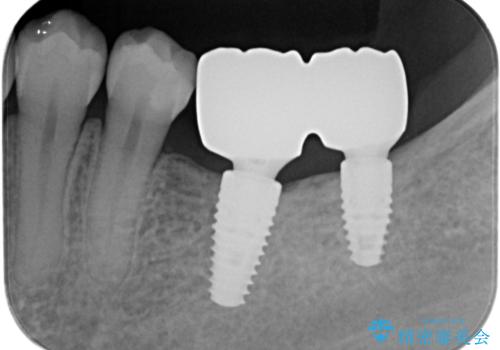

奥歯のインプラント

- 奥歯が二本欠損しており、その奥に親知らずが残っていました。

インプラントの一時手術と親知らずの抜歯を同時にしています。

親知らずはだいぶ後方にあり使うことが難しいため抜歯しています。